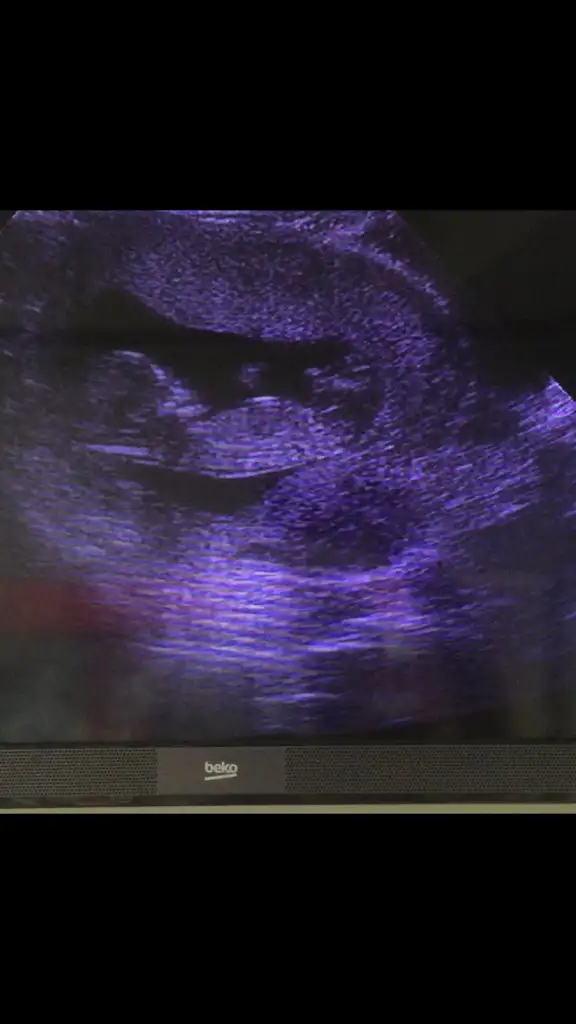

Biri kız biri erkeksordum ama daha erken dedibi de şimdi bunları ,çektim videodan belki yardımcı olur

Canım soldaki kız sağdaki erkek.foto da soldakinden emin olamamıştım videoda daha net.nub çizgisi göremiyorum.kafa yapılarına göre yorum yaptım.sonucu öğrenince yazarsınsordum ama daha erken dedibi de şimdi bunları ,çektim videodan belki yardımcı olur

teşekkürler canım.öğrenince yazacağımCanım soldaki kız sağdaki erkek.foto da soldakinden emin olamamıştım videoda daha net.nub çizgisi göremiyorum.kafa yapılarına göre yorum yaptım.sonucu öğrenince yazarsın

Sol erkek sağ kızsordum ama daha erken dedibi de şimdi bunları ,çektim videodan belki yardımcı olur